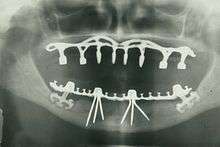

- Oral and maxillofacial radiology – The study and radiologic interpretation of oral and maxillofacial diseases.